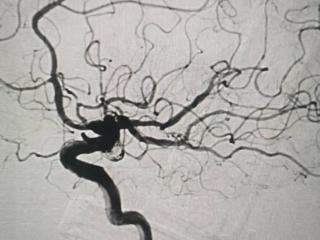

妙手“神龙摆尾”攻克手术难关——平度市第三人民医院成功为八旬老人完成高难度脑动脉瘤介入治疗